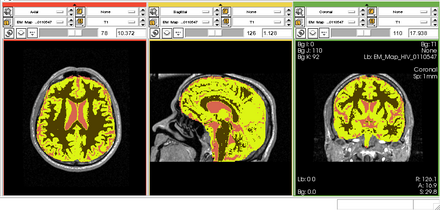

Brain Atrophy in HIV Patients

- Collaborator: Alexander Zaitsev (Brigham and Women's Hospital) and National HIV Consortium

- Short description: Evaluate Brain Atrophy in HIV Patients

- Image specification: 3 Tesla, Scanner: NA, MPRAGE, Sagittal Scans, TR/TI/TE=NA, pixel_xsize = 0.9375, pixel_ysize = 0.9375, fov = NA, aspect = NA, space = 1.5

- Used Task: MRI Human Brain